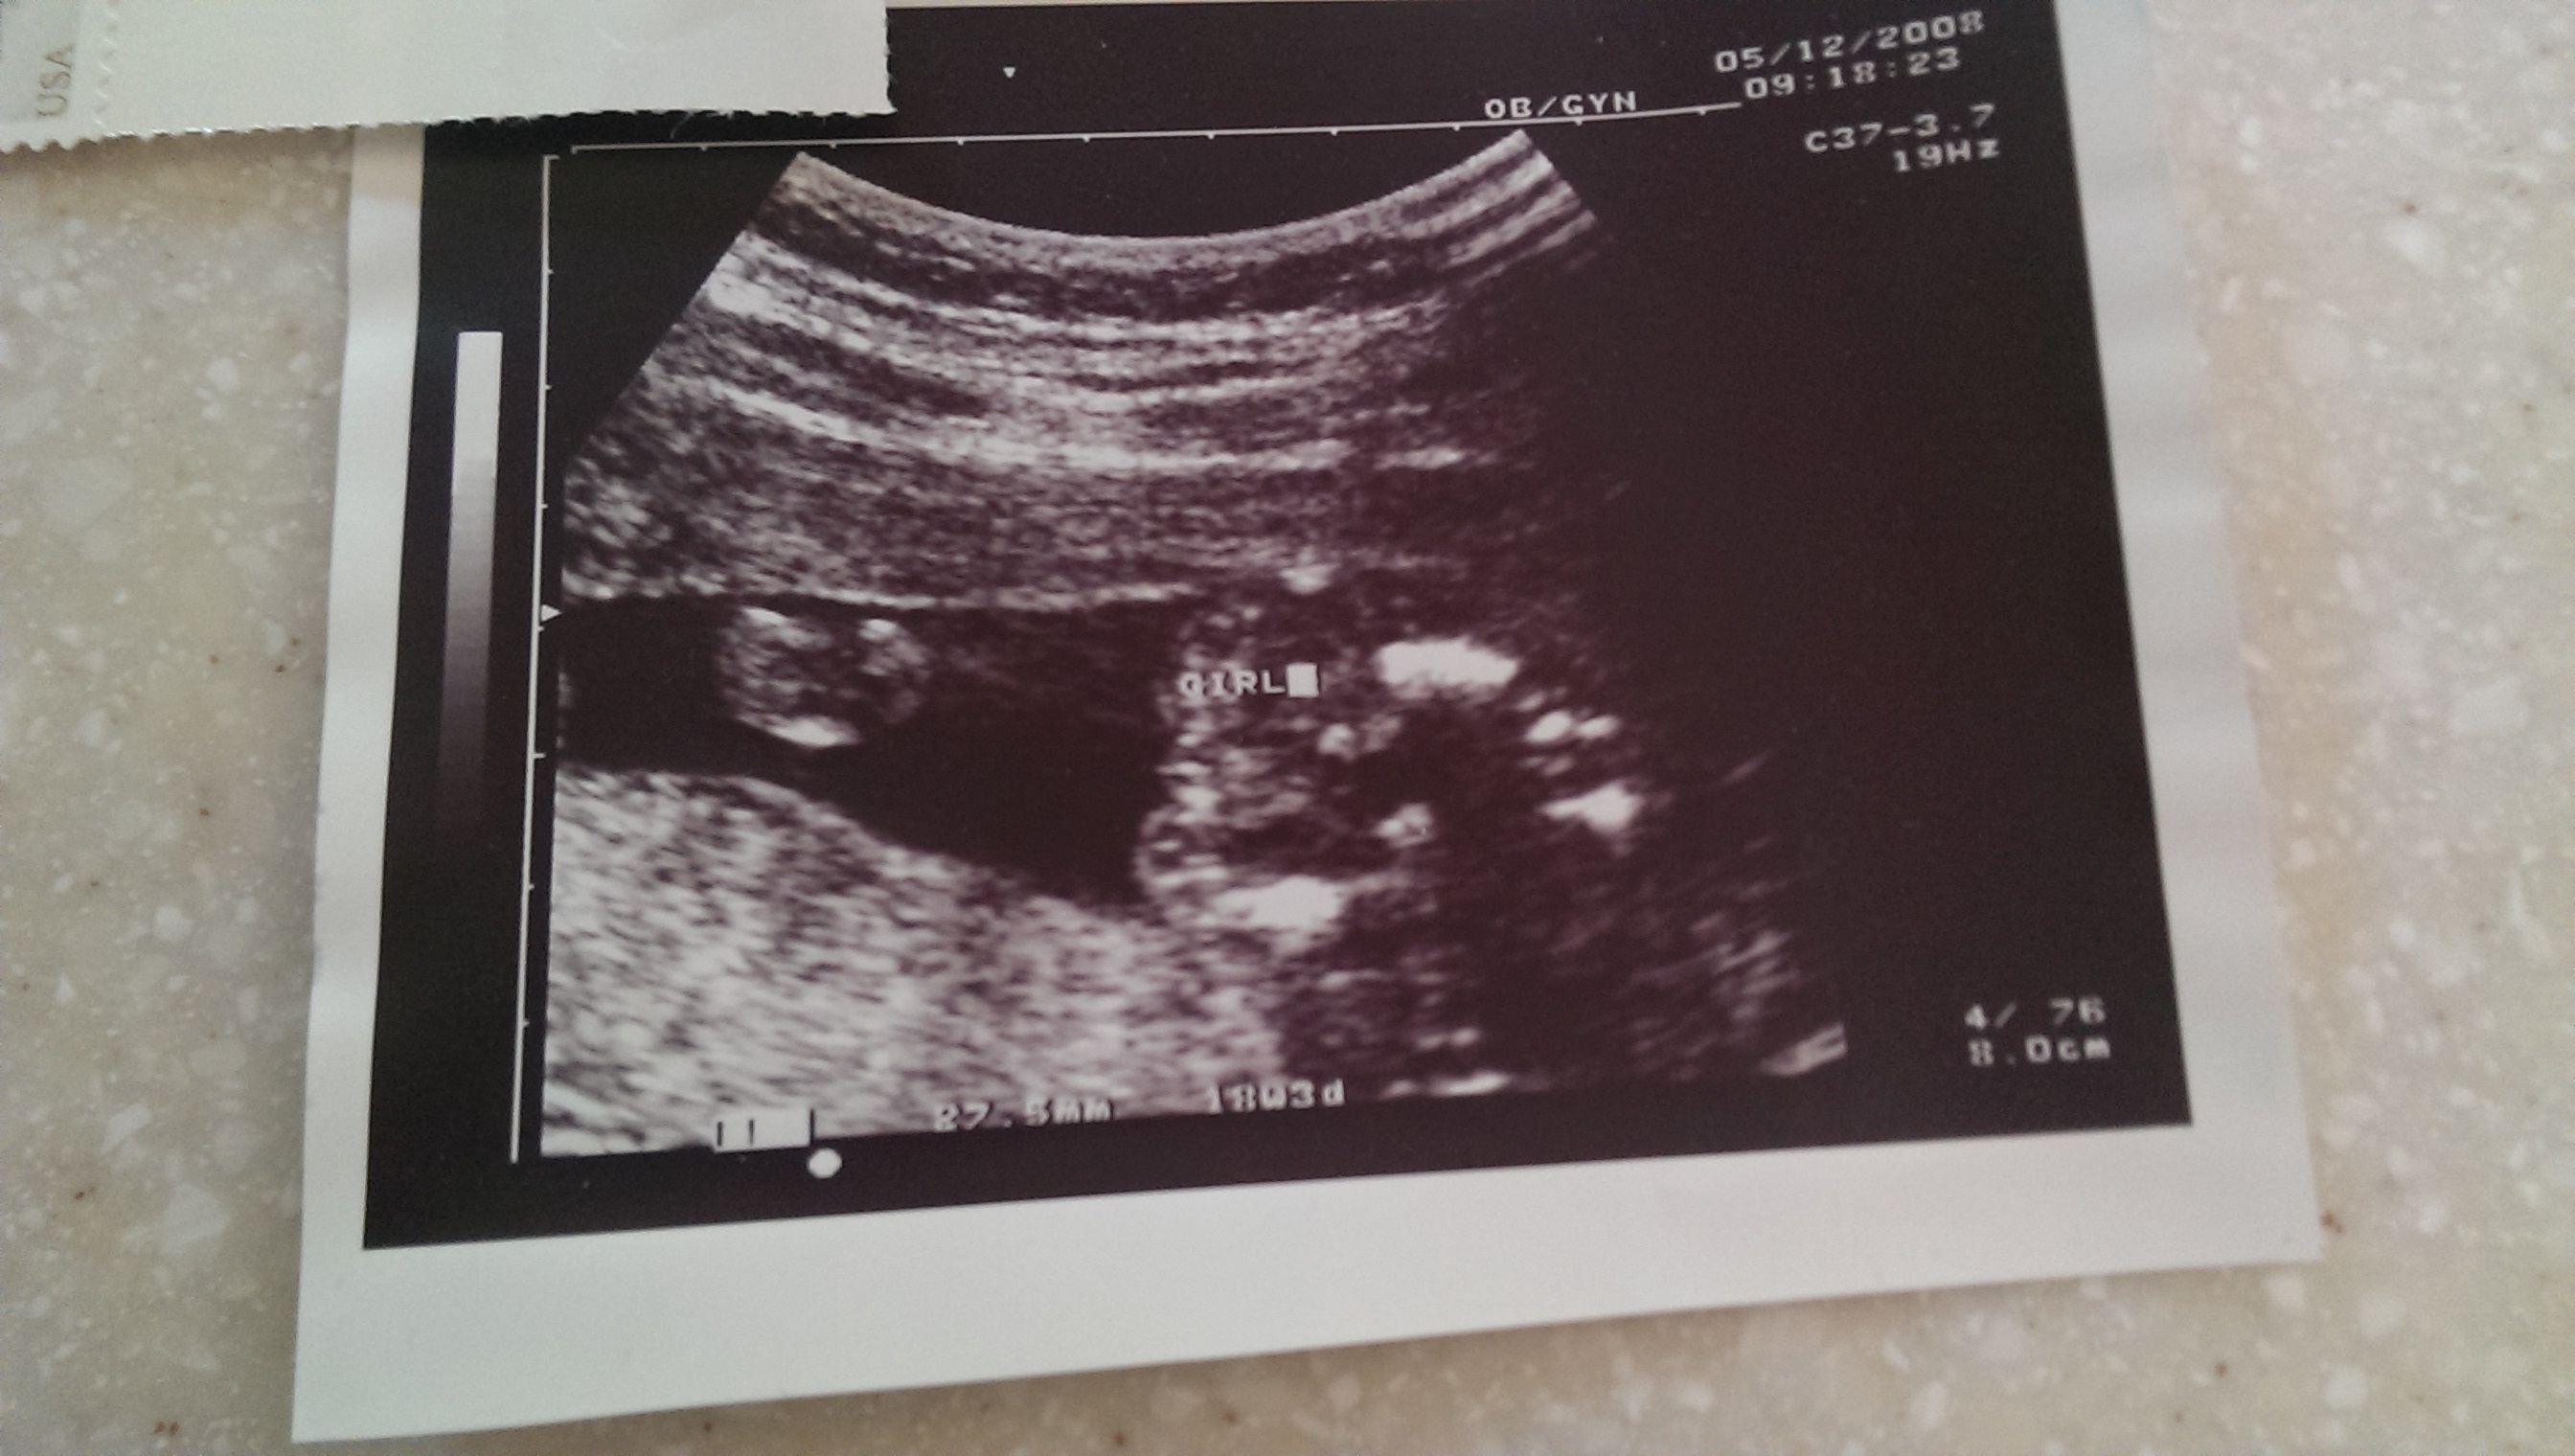

• I have this little gem from my first pregnancy (sorry I know how much everyone loves potty shots).  Anatomy u/s and the tech told us girl, never said 'maybe a girl' or anything, just congrats its a girl.  A few months later at another ultrasound we found out that he was most definitely a BOY.  We already had a girl nursery and some girl clothes, fortunately our large items were gender neutral.

Our other boys have been completely obvious at their ultrasounds, no doubting it.  This pregnancy is supposed to be a girl and even though I've had 2 u/s confirm that, I still feel nervous there's a penis hiding in there somewhere!